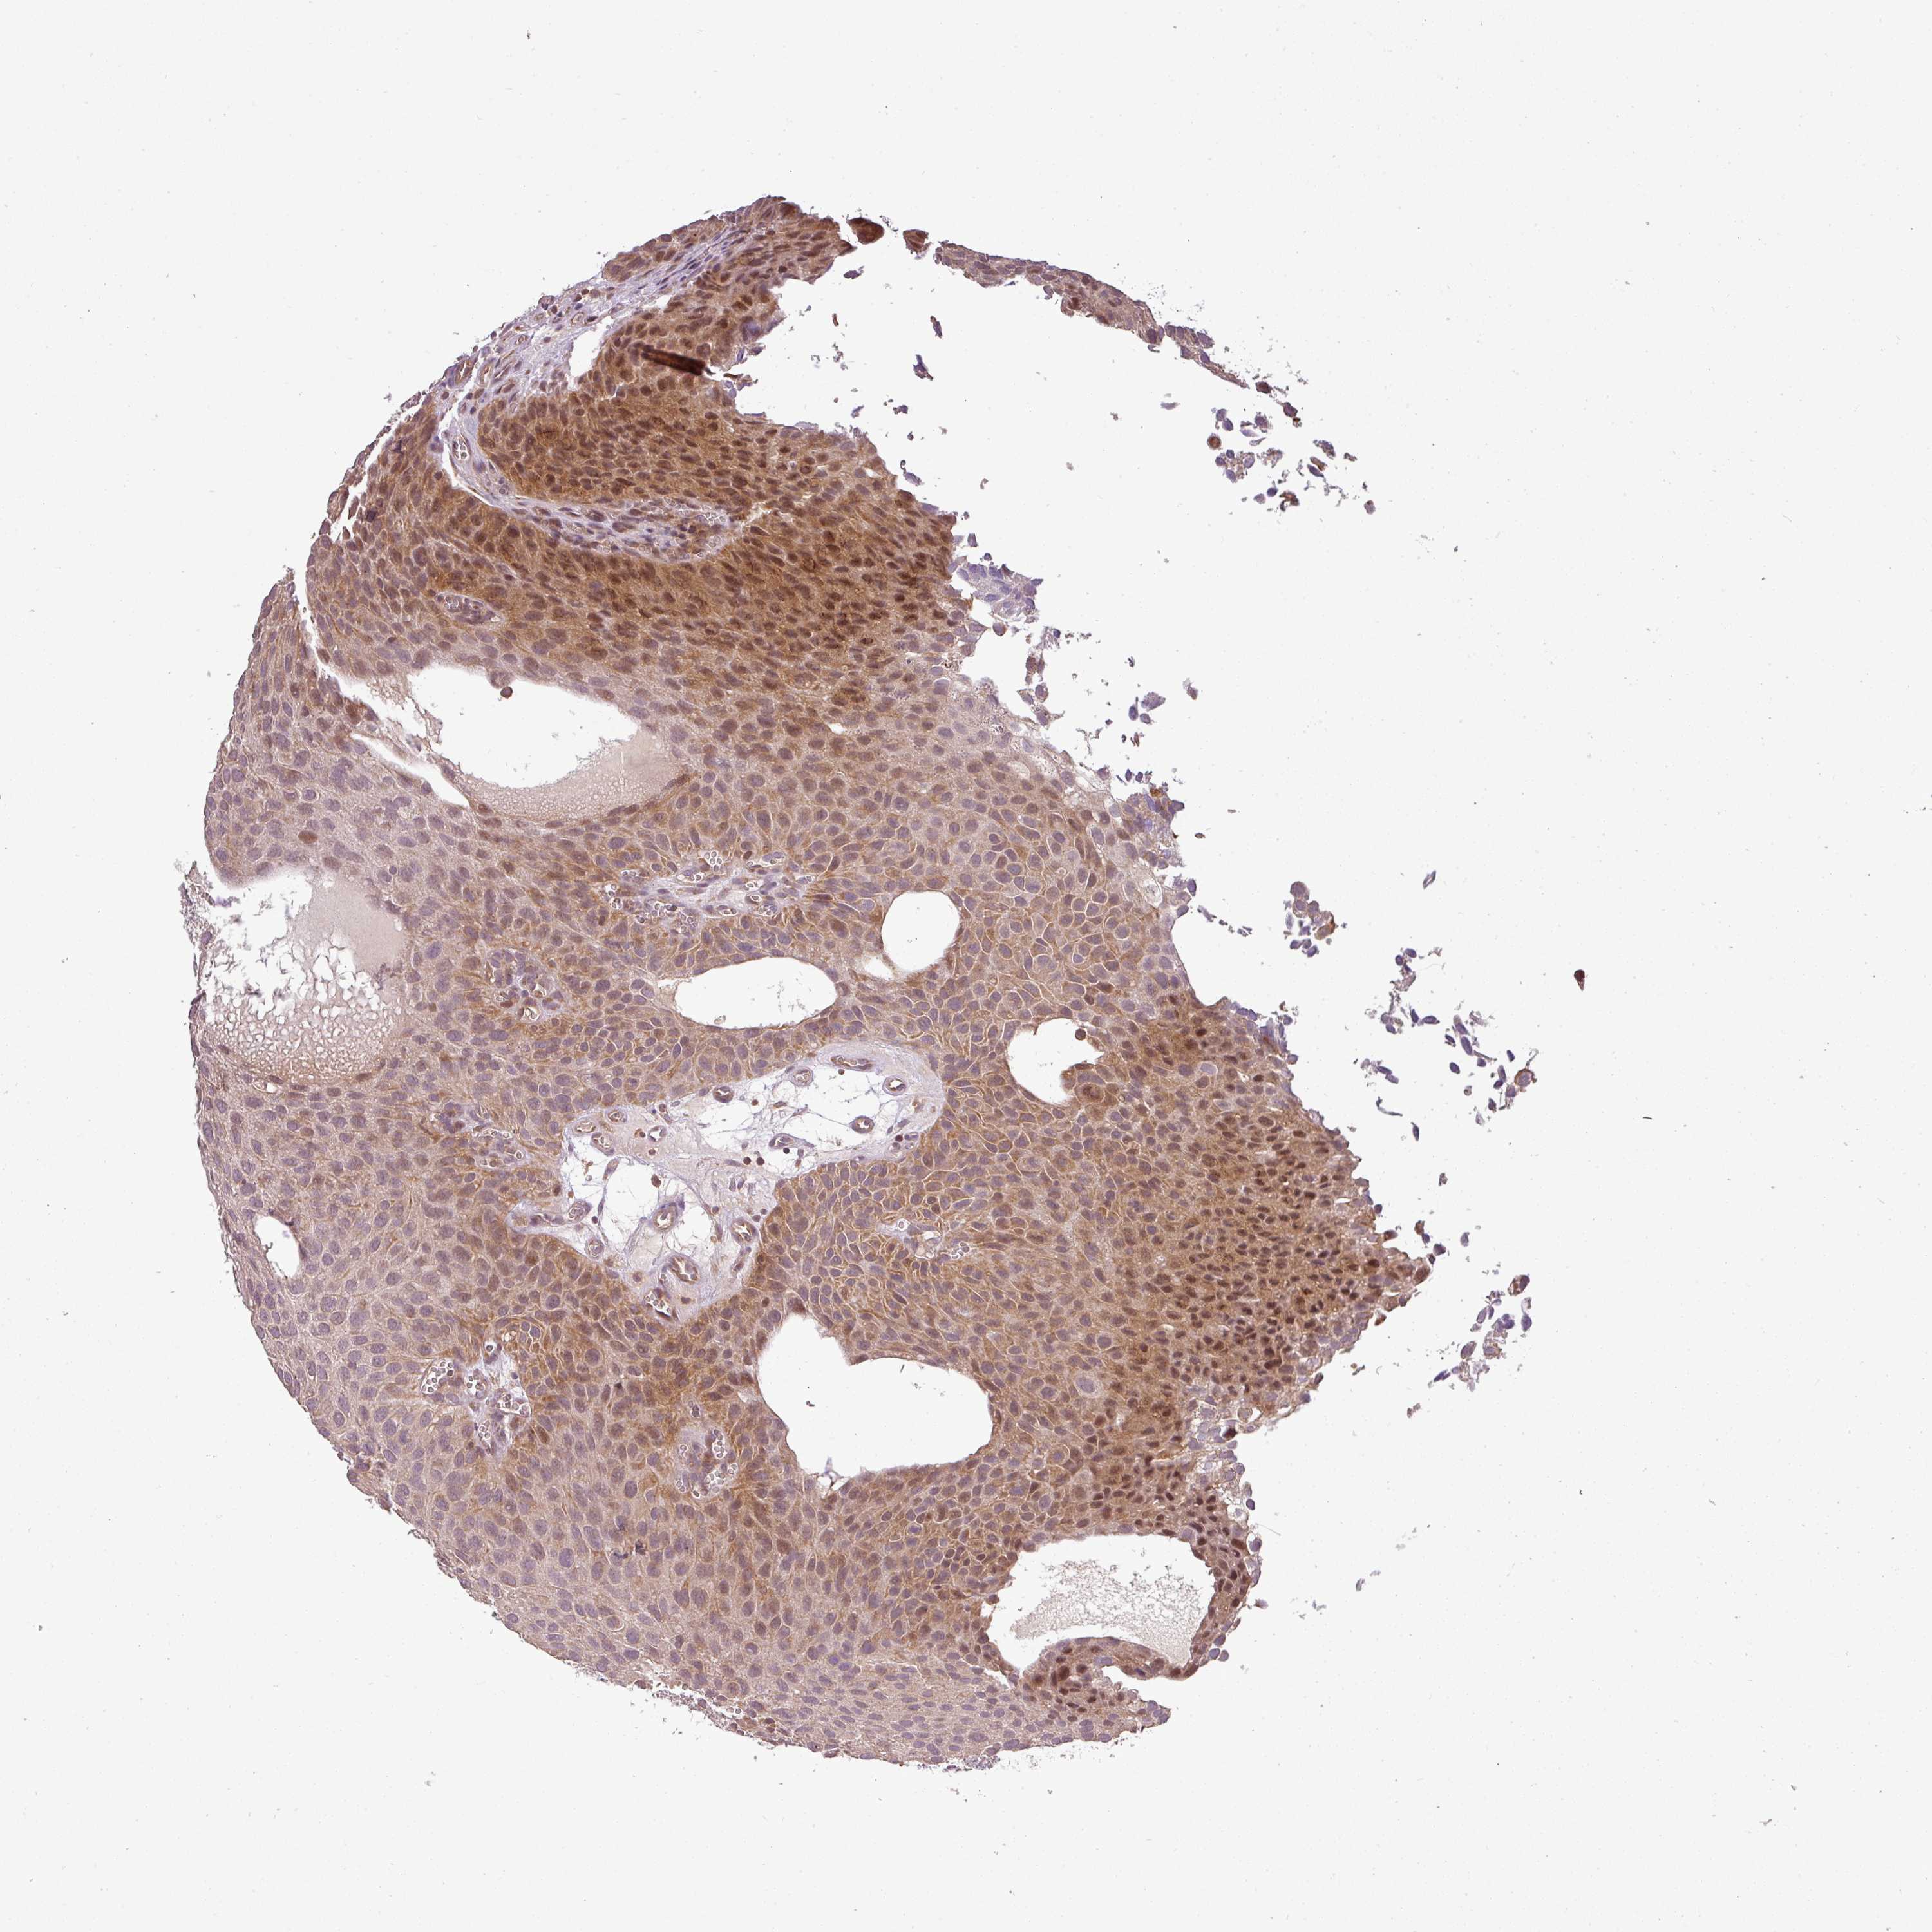

UROTHELIAL CANCER - Protein expressioni

A mouse-over function shows sample information and annotation data. Click on an image to view it in a full screen mode. Samples can be filtered based on level of antibody staining by selecting one or several of the following categories: high, medium, low and not detected. The assay and annotation is described here.

Note that samples used for immunohistochemistry by the Human Protein Atlas do not correspond to samples in the TCGA dataset.

Antibody stainingi

Antibody staining in the annotated cell types in the current human tissue is reported as not detected, low, medium, or high, based on conventional immunohistochemistry profiling in selected tissues. This score is based on the combination of the staining intensity and fraction of stained cells.

Each image is clickable and will lead to virtual microscopy that enables deeper exploration of all samples and also displays staining intensity scores, fraction scores and subcellular localization as well as patient and tissue information for each sample.

Antibody HPA042440

Antibody HPA052209

Staining

High

Medium

Low

Not detected

Intensity

Strong

Moderate

Weak

Negative

Quantity

>75%

75%-25%

<25%

None

Location

Nuclear

Cytoplasmic/membranous

Cytoplasmic/membranous,nuclear

Urothelial carcinoma, Low grade

Urothelial carcinoma, High grade

Urothelial carcinoma, NOS